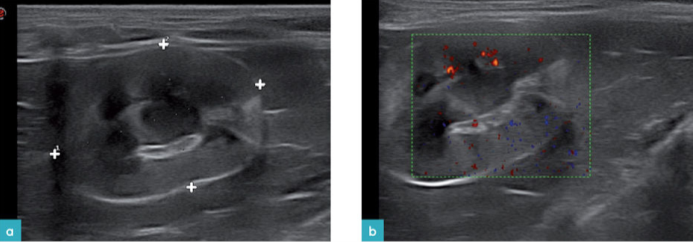

囊肿表现为圆形的无回声或低回声腔,通常位于肾皮质或髓质中,与实质能很好的区别开来,并具有薄壁(图18.视频9)。随着年龄增加直到最终囊肿甚至可以完全替代正常肾实质并引起肾损伤,而且囊肿的数量和大小变化很大。囊肿往往是中空的,但其中一些可能含有血液,或者可能存在低回声或内部回声(图19.视频10)。